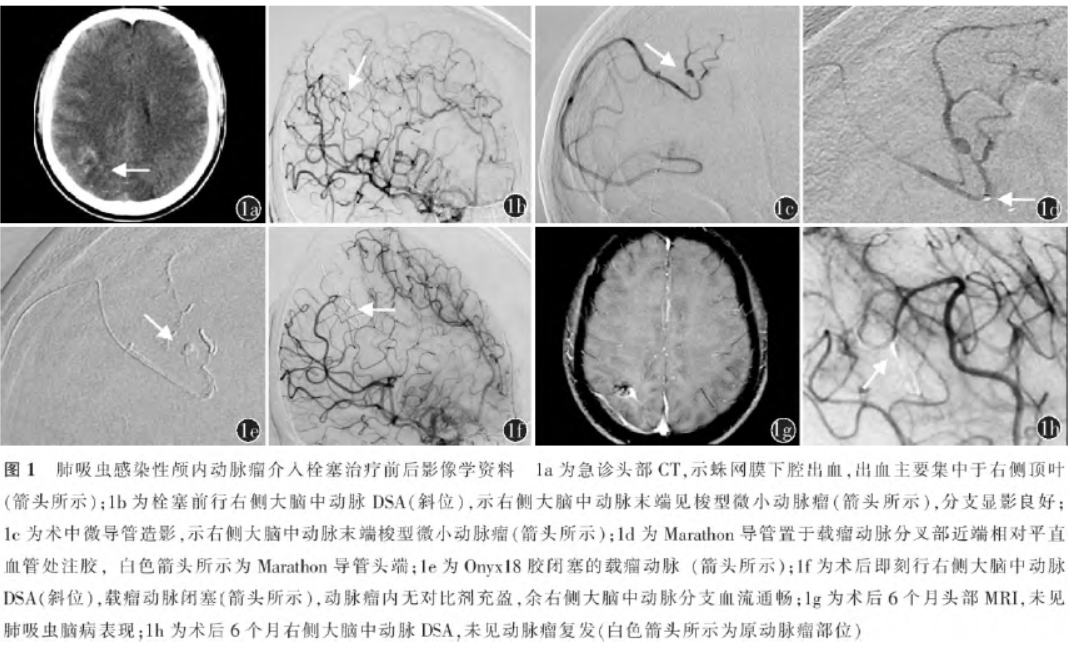

介入栓塞治疗肺吸虫感染性颅内动脉瘤一例

病史摘要:27岁男性患者,主诉“反复发热、咳嗽、咯痰3个月伴突发头痛3d”。既往半年前有生吃溪蟹史。诊疗过程:入院查体意识清楚,无皮下结节,双下肺叩诊浊音,颈强直。急诊头部CT示蛛网膜下腔出血。住院后全脑DSA示右侧大脑中动脉末端动脉瘤;胸部CT示双肺感染等;实验室检查血清肺吸虫IgG抗体阳性,血常规嗜酸性粒细胞比例升高等。诊断为感染性颅内动脉瘤肺吸虫病。行右侧大脑中动脉M4段动脉